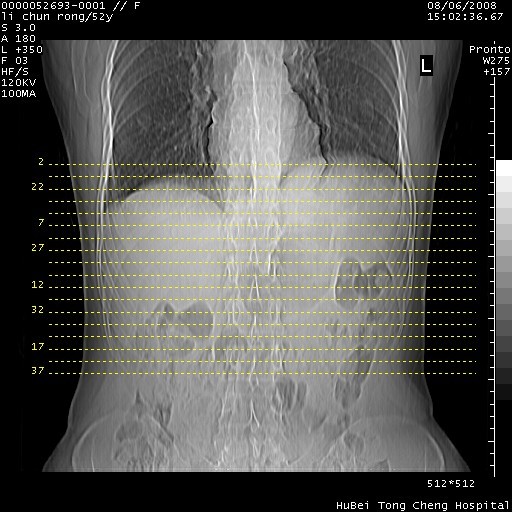

以下是引用云翔在2008-8-7 6:20:00的发言:[br]胰尾部囊性病变,考虑假囊肿,结合实验室检查疾病史

以下是引用zjzjr在2008-8-7 8:38:00的发言:[br]支持胰腺炎伴假囊肿形成,左肾小囊肿.少量腹水.

以下是引用随光逐影在2008-8-7 9:12:00的发言:[br]1)考虑胰腺炎伴假性囊肿形成可能性大;胰腺囊腺瘤待排。2)左肾小囊肿。3)少量腹水。